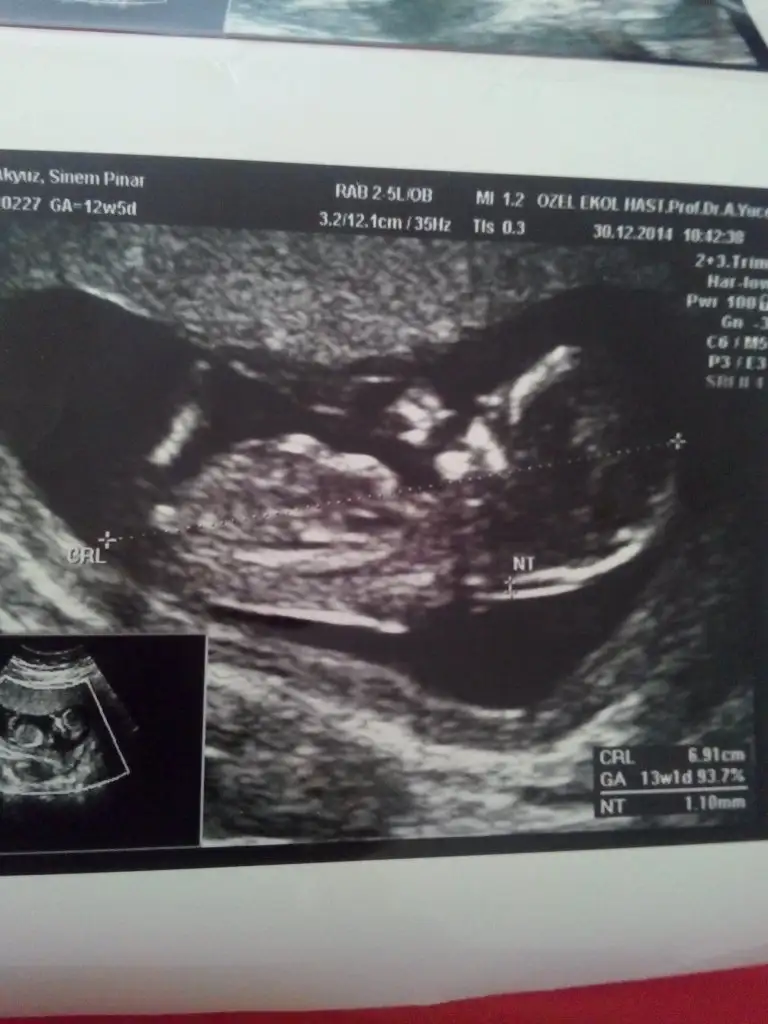

kızlar sizce benmki kızmı erkekmi tam erkek gbi değil derecesi ama kız gbide değil sanki ya :D çözemedm var bsy orda ama IMG_20141230_131619.webp

zeynep doktorum bugun izinliymiş gıdemedim kafayı yedim sanırım yarında yoktur ama arıcam yıne kısmet degılmiş bugun ne dıyelim artık cumaya kaldı heralde senin tahminin hala kızmı?